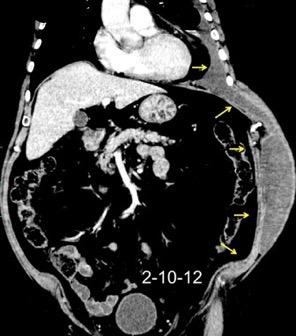

Comunica con el hiato esofágico y el espacio pararrenal anterior.

Colecciones “inflamatorias” abdominales llegan al tórax vía el hiato esofágico o por vía transdiafragmática

Afectación transdiafragmática: 5,6-43,7% de quistes hepáticos. “Área desnuda” del hígado.

Panda A et al. “Straddling Across Boundaries”. Thoracoabdominal Lesions: Spectrum and Pattern Approach. Curr Probl Diagn Radiol. 2015 Área desnuda. El hígado en contacto directo con el tendón central del diafragma. Contiene el hiato de VCI.